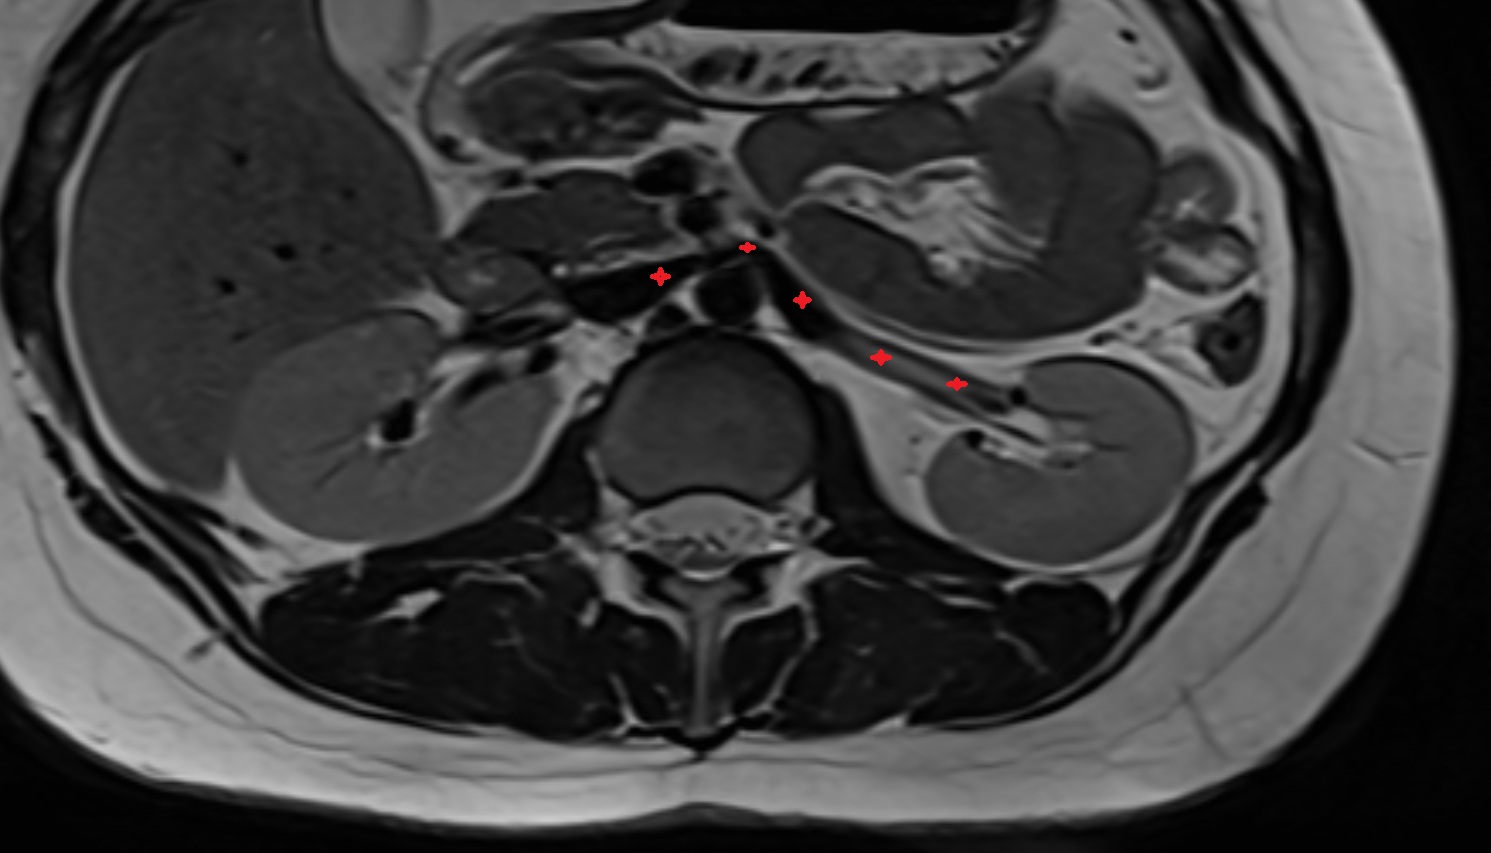

- kidneys

- Right kidney

- Left kidney

- Kidney cortex (Renal cortex)

- Renal capsule

- Renal medulla

- Renal pyramids

- Ureters

- Left ureter

- Right ureter

- Renal artery

- Renal vein

- Left renal vein

- Right renal vein

- Left renal artery

- Right renal artery